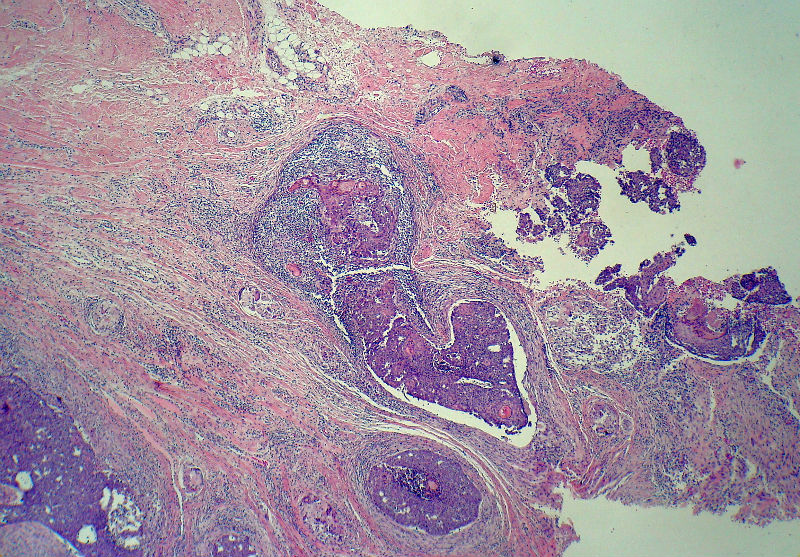

男,49岁,后枕部肿物3年,偶有破溃出血。

大体:皮肤半球形隆起,大小约2.3×2厘米,高出皮表0.8厘米,切面灰白,质地细腻。

似乎既有腺样结构,也有角化珠形成,还有细胞团内的粉刺样坏死。

有坏死、囊肿、钙化及胆固醇样裂隙等结构

考虑外毛根鞘肿瘤,局部癌变。